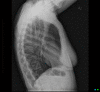

Contraceptive implant migration into the pulmonary circulation is an uncommon, but potentially serious complication. We describe an "aspiration" technique for percutaneous retrieval of a contraceptive implant from a subsegmental pulmonary artery, using a Penumbra Neuron MAX 088 guiding catheter and a Merit Medical VacLok Vacuum Pressure Syringe, as an alternative to the previously described snare technique. Our patient had an uneventful recovery and was discharged home on the same day.